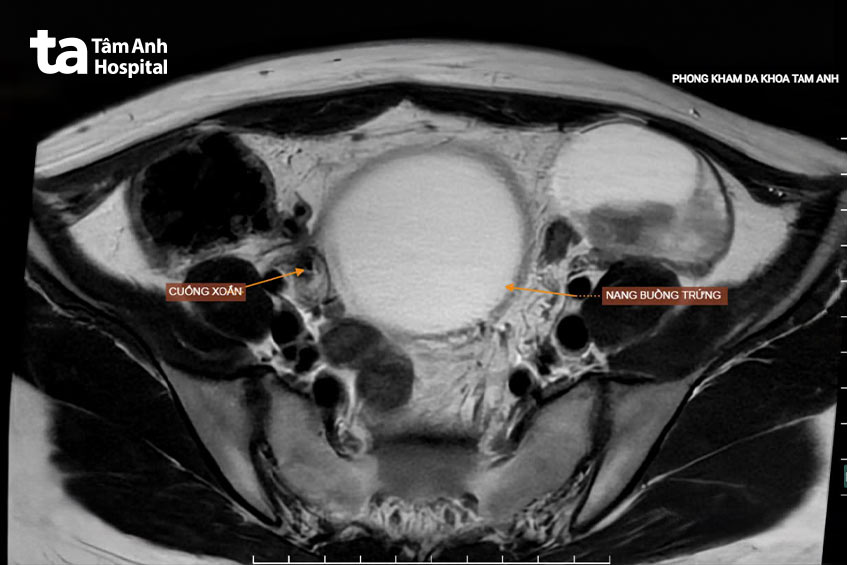

BS.CKI Hồng Văn In, Trưởng đơn vị Cấp cứu, cho biết dấu hiệu lâm sàng cho thấy chị Thùy xoắn buồng trứng. Kết quả chẩn đoán hình ảnh bệnh nhân phì đại buồng trứng hai bên, trong đó buồng trứng phải rất to, kích thước 10x12x12 cm, gấp 5 lần bình thường (kích thước buồng trứng trung bình cỡ 2x2x3 cm).

Theo bác sĩ In, chị Thùy bị xoắn buồng trứng bên phải, tức một bên buồng trứng xoắn xung quanh các dây chằng giữ nó. Bệnh có thể liên quan đến hội chứng quá kích buồng trứng sau dùng thuốc kích trứng trong quá trình điều trị hỗ trợ sinh sản, có khả năng đe dọa tính mạng với tỷ lệ mắc là 0,02% trong thai kỳ.